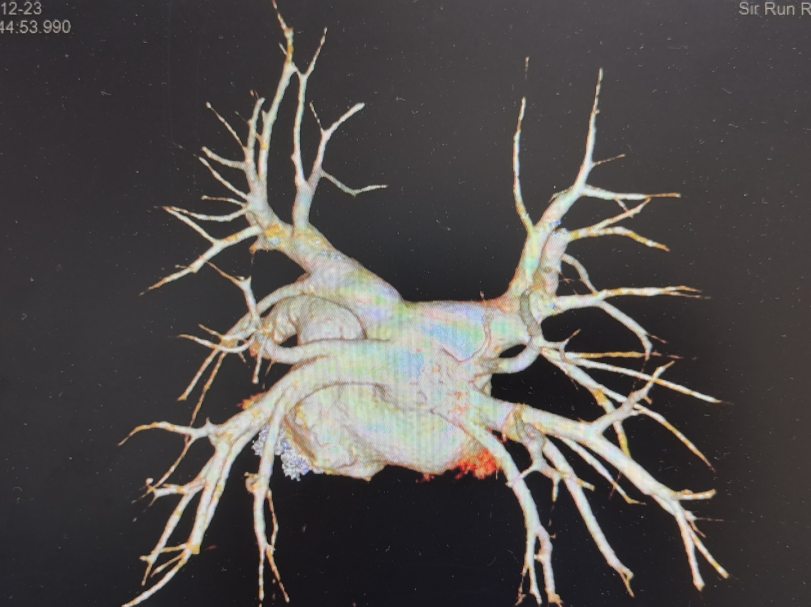

CTA

术式内容:AgileView™ ICE(腔内超声)实时影像指导下,脉冲消融导管完成肺静脉隔离(PVI),并进一步行顶部线及左房后壁,上腔静脉消融

导管组合:AgileView™ ICE导管用于术前筛查,术中心房结构显示、房间隔穿刺指导及导管贴靠(封堵)判断PulseSelect™ 脉冲消融导管用于肺静脉隔离及肺外消融